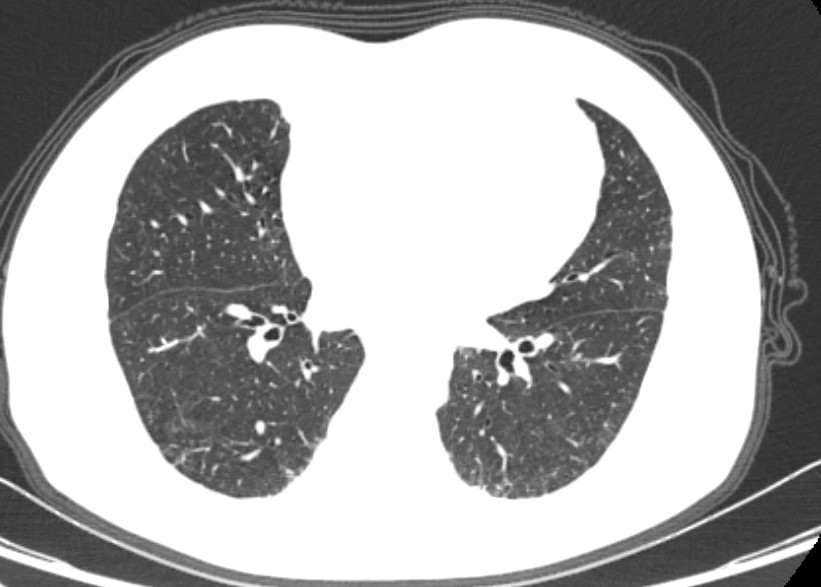

有见过类似病历的吗? [病例帖]

图片尺寸744x992